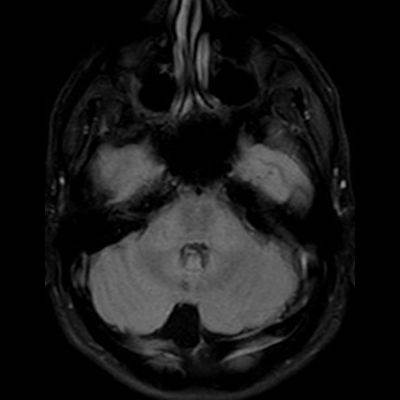

11 ay, Nöbet

Charlevoix-Saguenay Otozomal Resesif Spastik Ataksisi (ARSACS)

Charlevoix-Saguenay Otozomal Resesif Spastik Ataksisi ARSACS

ARSACS (Charlevoix-Saguenay otozomal resesif spastik ataksisi) Sendromu

Serebellar folya sinapsisi